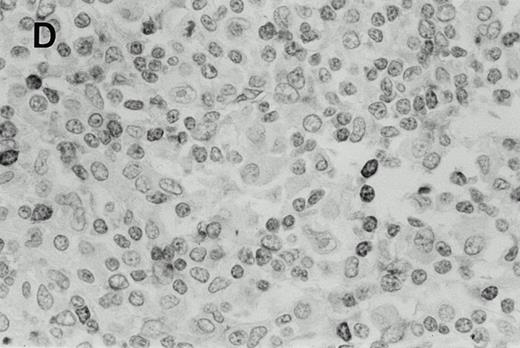

Immunohistochemistry of CD3 in case 1: (A) low (40×), (B) high (400×). CD3+ T cells are associated with clusters of H-RS cells, often forming a ring around the H-RS cells. Inset shows CD30+ H-RS cells. Immunohistochemistry of MB2 in case 2: (C) low (40×), (D) high (400×). MB2+ CLL cells are present around a nodule of HD. H-RS cells are admixed with T cells and histiocytes and only scattered MB2+ small lymphocytes are present.

The results of the immunohistochemical studies are shown in Table1 and Fig 2.The CLL cells were reactive with B-cell markers in all three cases, and also expressed CD43 in cases 2 and 3, as is commonly observed in B-CLL.23 The H-RS cells expressed CD15 and CD30 in all three cases. In case 1, a small subset of the H-RS cells also expressed CD20. The small lymphocytes forming the inflammatory background of the HD component in cases 2 and 3 were mostly T cells. Scattered B lymphocytes were also present, more prominently in case 2 where the Hodgkin's foci were less sharply demarcated from the CLL areas as compared with case 3. In case 1, although the typical cellular background of HD was absent, most of the small lymphocytes associated with the H-RS cell areas were T cells which often formed a ring around the H-RS cells.